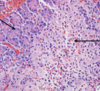

On histology, pancreatic adenocarcinoma appears _

On histology, pancreatic adenocarcinoma appears as **disorganized glandular structure with cellular infiltration**